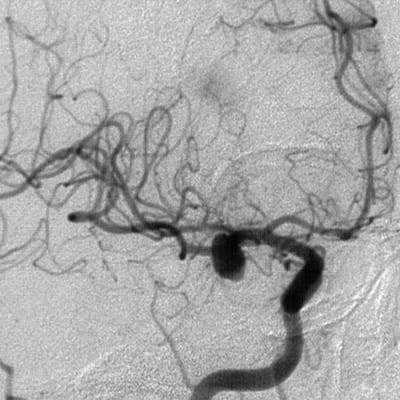

В большинстве наблюдений (у 32 из 38 больных) при АА офтальмического, коммуникантного и хориоидального сегментов ВСА ВЭСА на этапе арахноидальной диссекции и выделения аневризмы была эффективна для осмотра нижней поверхности ВСА, определения расположения устьев задней соединительной артерии (зСоА) и передней ворсинчатой артерии (ПВА), уточнения формы АА и возможности ее клипирования. После клипирования аневризмы ВЭСА позволяла исключить компрессию ветвей ВСА и удостовериться в полном перекрытии шейки аневризмы браншами клипсы (рис. 1, 2).

Рис. 1. Клипирование аневризмы левой внутренней сонной артерии (ВСА) из левостороннего птерионального доступа. а — вид через микроскоп после клипирования аневризмы хориоидального сегмента левой ВСА; б — вид через эндоскоп с тубусом 30° из ретрокаротидного промежутка. 1 — левый зрительный нерв, 2 — левая ВСА, 3 — клипса на шейке аневризмы, 4 — устье задней соединительной артерии, 5 — устье передней ворсинчатой артерии, 6 — наконечник аспиратора.

Рис. 2. Клипирование аневризмы офтальмического сегмента левой внутренней сонной артерии (ВСА). а — магнитно-резонансная ангиограмма, вид сзади: аневризма офтальмического сегмента левой ВСА (указано стрелкой); б — вид через микроскоп: аневризма ВСА клипирована фенестрированной клипсой (указано стрелкой); в — вид через эндоскоп: клипса перекрывает шейку АА у основания (указано стрелкой), ствол ВСА не деформирован.